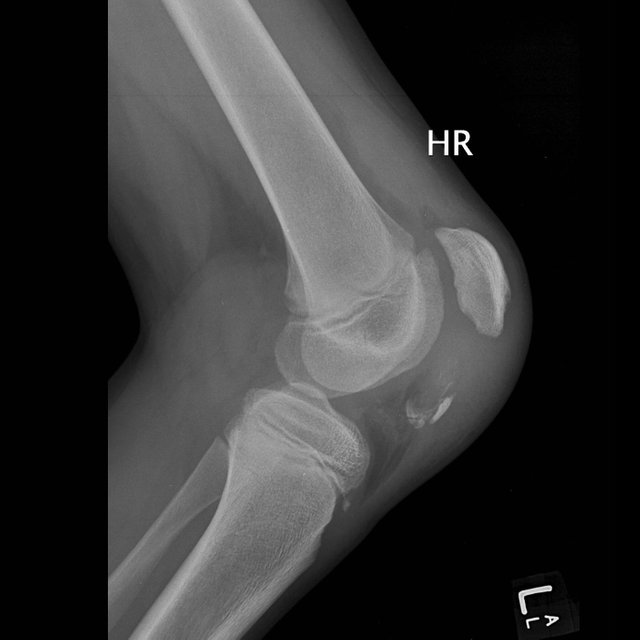

Q3

What sort of fracture is this?

An avulsion fracture of the patella (knee cap)